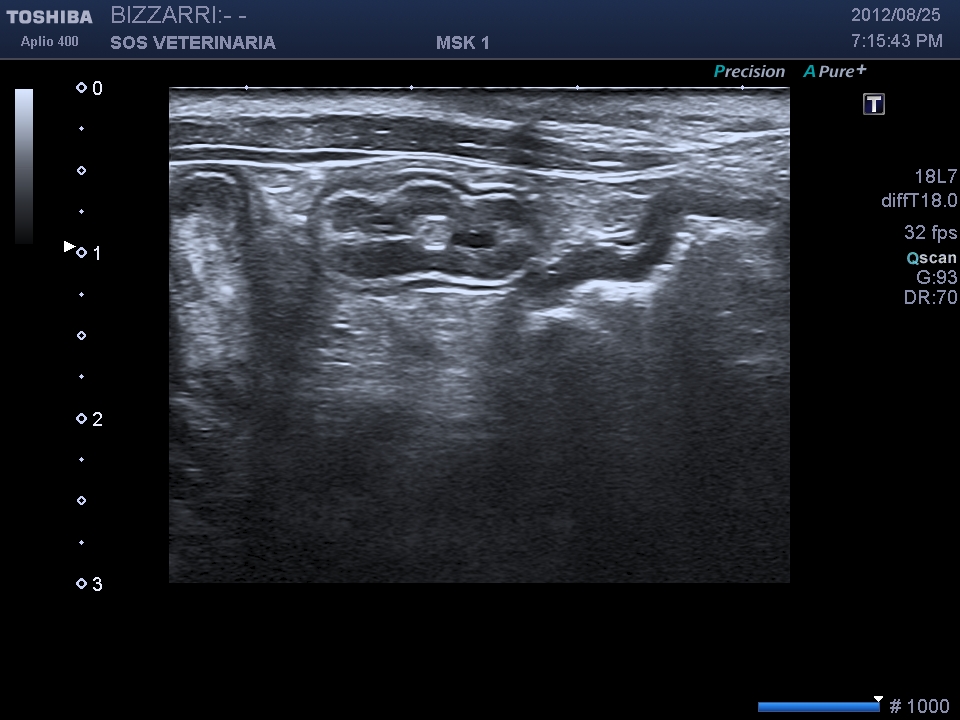

In presenza di sintomi gastroenterici acuti nei soggetti di giovane eta’, le sonde ad alta frequenza che la tecnologia di oggi ci mette a disposizione, ci permettono di vedere parassiti all’interno del lume intestinale che non devono essere confusi con corpi estranei lineari spesso responsabili di sindromi enteriche che richiedono chirurgia.

L’ascaride si differenzia ecograficamente dal copo estraneo filiforme per la presenza della parete esterna (cuticola) ,una parte interna parenchimale e l’assenza di cono d’ombra ,inoltre l’intestino puo’ essere spastico ma mai circonvoluto con pattern a fisarmonica.